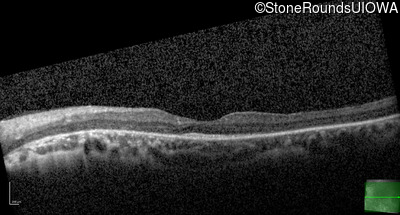

Optical Coherence Tomography - Right - 20/125 -1

Exemplar / OCT Stack